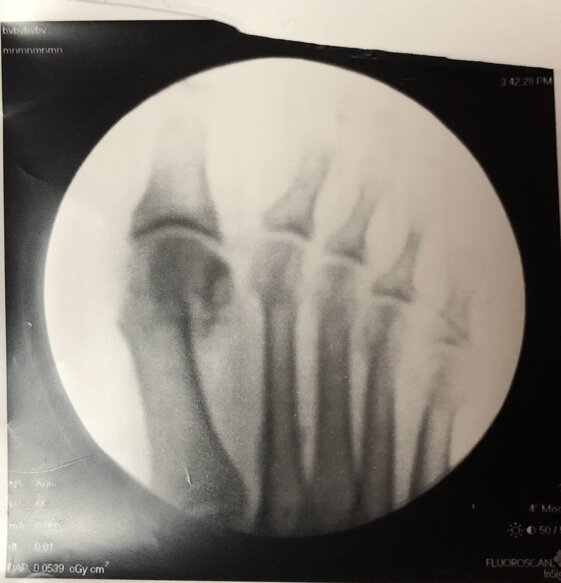

Radiografie post-operatorie in AP e LL di intervento di correzione di Alluce Valgo con tecnica mini-invasiva senza utilizzo di mezzi di sintesi metallici. Per l’osteotomia di correzione del I MT ho utilizzato un pin riassorbibile che quindi non è visulizzabile alle radiografie, mentre per l’osteotomia della prima falange del primo dito non ho utilizzato alcun mezzo di sintesi

Radiografie post-operatorie in AP di due interventi di correzione di Alluce Valgo con tecnica mini-invasiva senza utilizzo di mezzi di sintesi metallici. Per l’osteotomia di correzione del I MT ho utilizzato in entrambi i casi un pin riassorbibile che quindi non è visulizzabile alle radiografie. Nel caso a sinistra per l’osteotomia della prima falange del primo dito non ho utilizzato alcun mezzo di sintesi, nel caso a destra non ho effettuato l’osteotomia in quanto era presente un alluce valgo meno grave